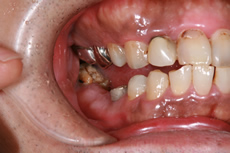

インプラント症例

術前